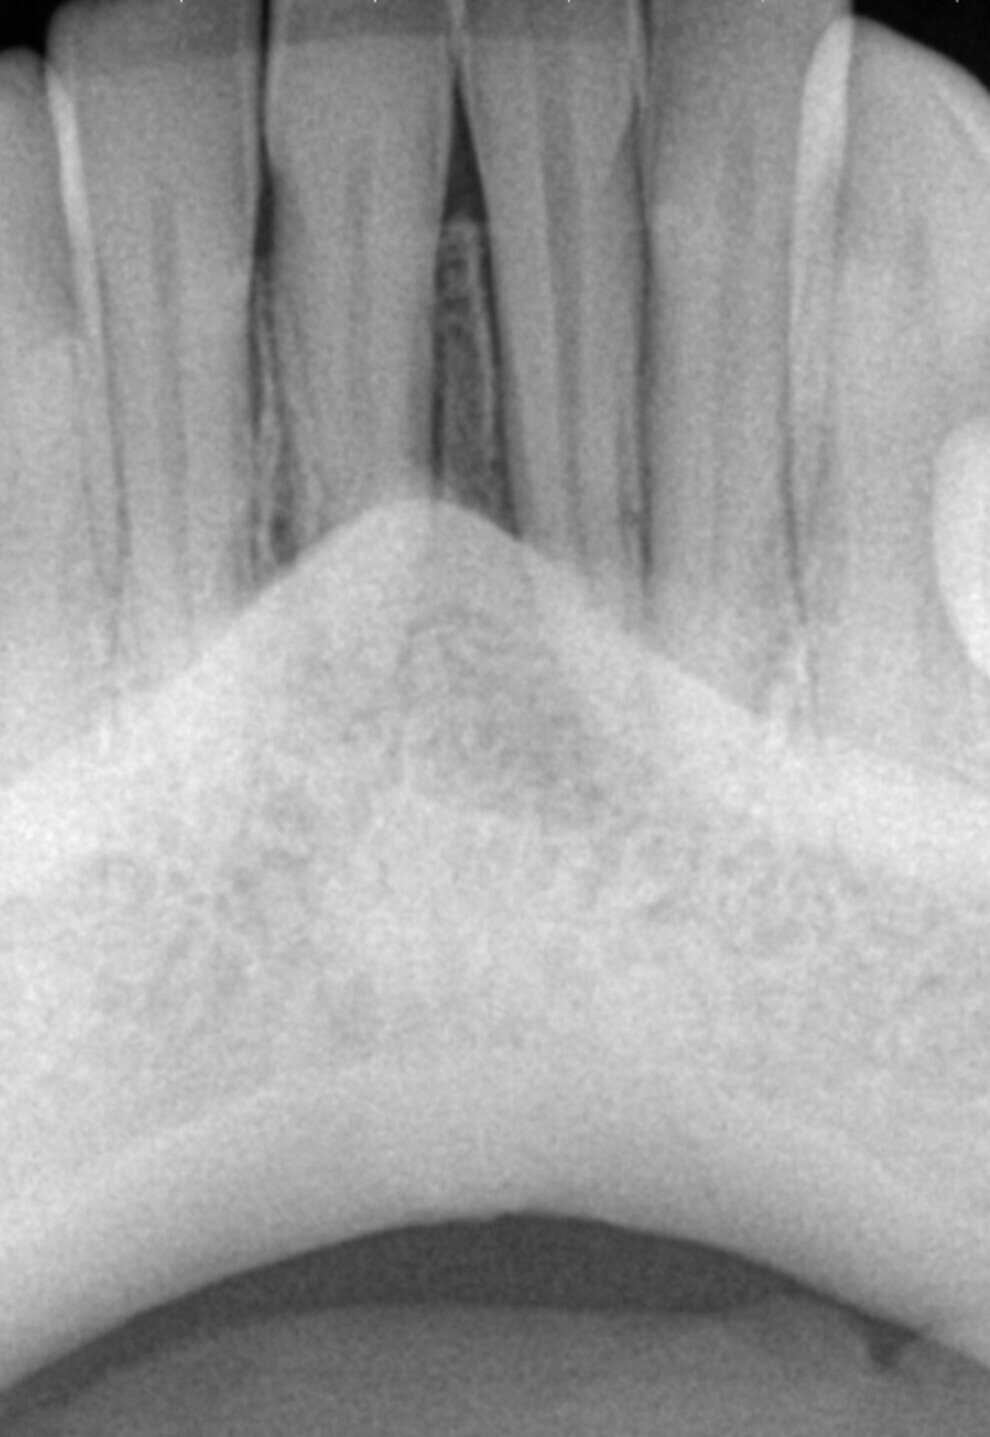

A radiograph was taken of the immediate postoperative situation and at the nine-month follow-up. Comparison showed bone apposition between the two central incisors (Fig. 4). An i-CAT scan was also taken at the nine-month follow-up to check the bone growth. The horizontal view, taken at the same level as that taken preoperatively, clearly showed the reduction of the gap from 14.11 mm to 4.42 mm at the cortical level and the trabecular bone showed the same trend in healing (Fig. 5). The vertical view showed that the bone on the buccal plate was growing towards the root and growing vertically (Fig. 6). Almost 8.2 mm in height had been regained and in direct contact with the roots of the teeth. Indeed, when provided with a scaffold on which to grow, the bone can grow in all directions, including vertically, where there was an open periodontal pocket. This is the major breakthrough of this technique. No bone grafting material or a membrane was placed. The periosteum was in great condition, and for me, it was the best membrane I could wish for.

Fig. 5a: Comparison of the horizontal views of the i-CAT scans taken pre-op ....

Fig. 5b: ...and at the nine-month follow-up.